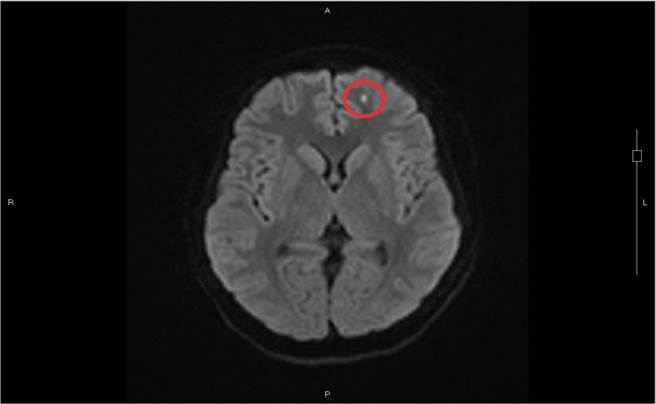

沉积在脑部左边额叶脂肪粒(红圈处),导致少年出现情绪症状。(光田综合医院提供/陈淑娥台中传真)

严可伦解释,股骨(大腿骨)、胫骨(小腿骨)是人体的长形骨,骨头中央有着脂肪丰富的骨髓,当病患骨折时,这些脂肪粒从断骨处释放散出,随着血液回流后先经过肺臟,因此脂肪栓塞常常发生在肺部,病人会出现喘不过气、血氧降低等症状,但阿成完全没有肺部症状,脂肪意外卡在脑部。

黄炳钟说明推测病患可能年轻,骨髓中的脂肪粒微小,通过肺部后再随血液至脑部而沉积在左边额叶及右边颞叶,这两处都与情绪处理相关连,因而出现情绪症状。